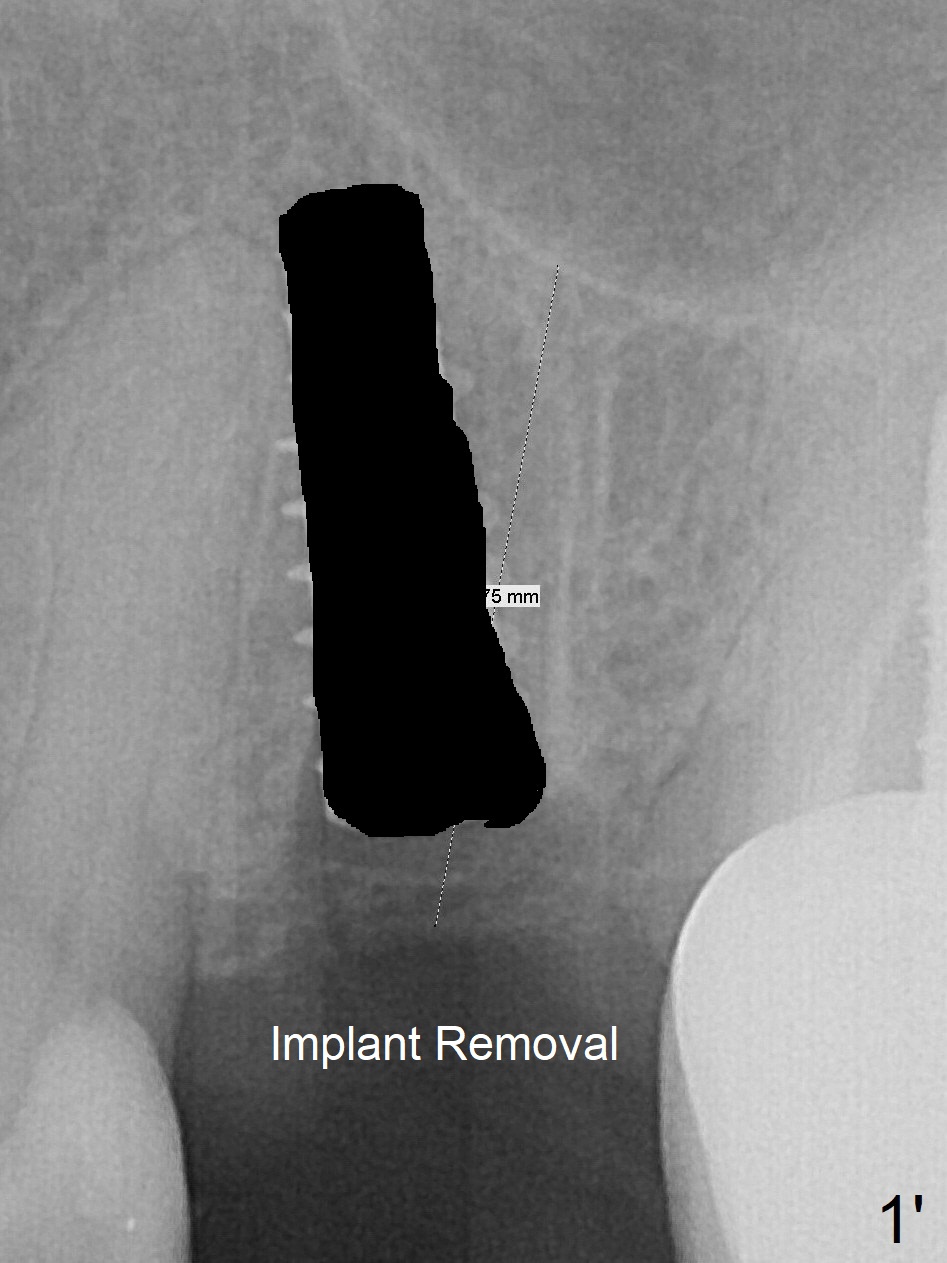

Since the apical native bone is limited at #13 after extraction, no PA is taken until a 4x11 mm dummy implant is placed after 1.6 mm and 3.3 mm drills for 13 mm (Fig.1). The trajectory needs to be changed.

First, the implant is removed (Fig1'). Move the osteotomy distal by using Lindamann bur (Fig.1''). Remove the Lindamann bur (Fig.1'''). Reuse 3.3 m Magic Drill (Fig.1''''). After using Lindamann bur to move the osteotomy distal and reusing 3.3 mm drill, the trajectory of a 4.5x11 mm IBS dummy implant improves (Fig.2 with low stability).